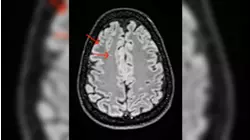

Now Playing3minKim Kardashian's brain aneurysm revelation brings light to the diagnosis

Now Playing3minKim Kardashian reveals she was diagnosed with a brain aneurysm